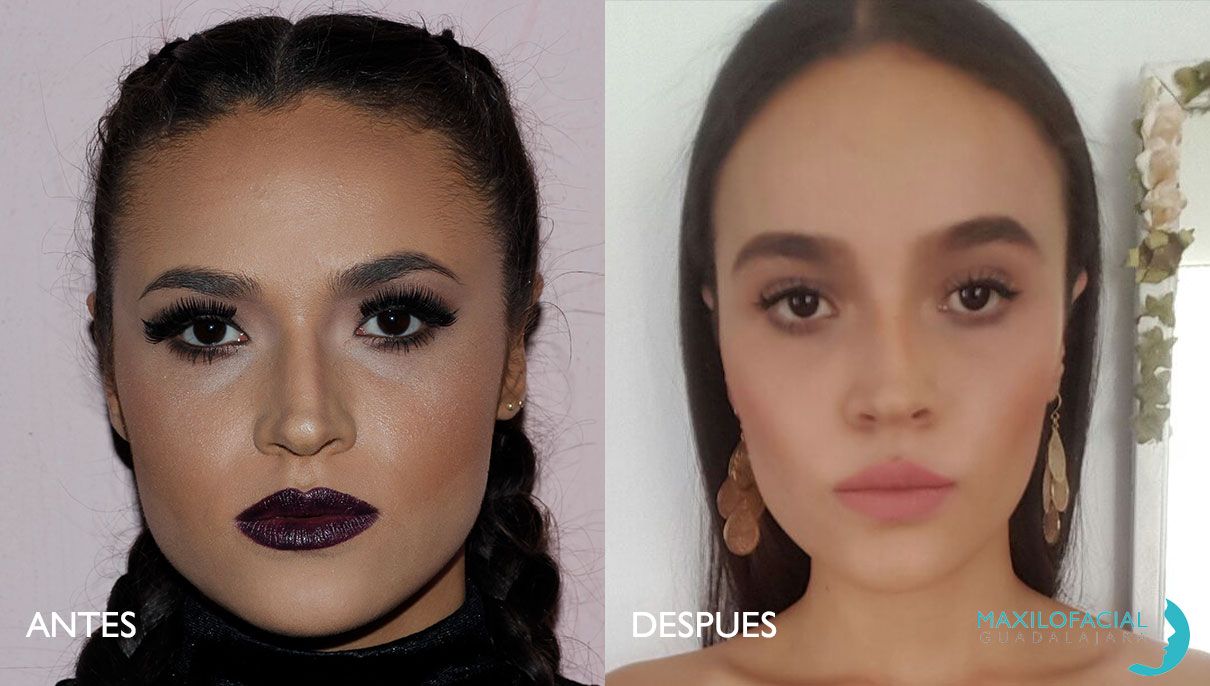

Bichectomía

La extracción de la bola de bichat es el medio más seguro de reducir el exceso de grasa de las mejillas. El resultado de la cirugía es una apariencia facial más delgada, con pómulos más definidos.

La cual se realiza mediante anestesia local. Dentro de la boca se hace una pequeña incisión en el vestíbulo superior del labio a la altura de los molares. A través de esta incisión se extrae la bolsa. Suturando más tarde la zona de incisión. La recuperación precisa de unos días para que la inflamación baje a niveles normales. Posteriormente con el paso del tiempo y la disminución del edema se adelgaza progresivamente la mejilla.